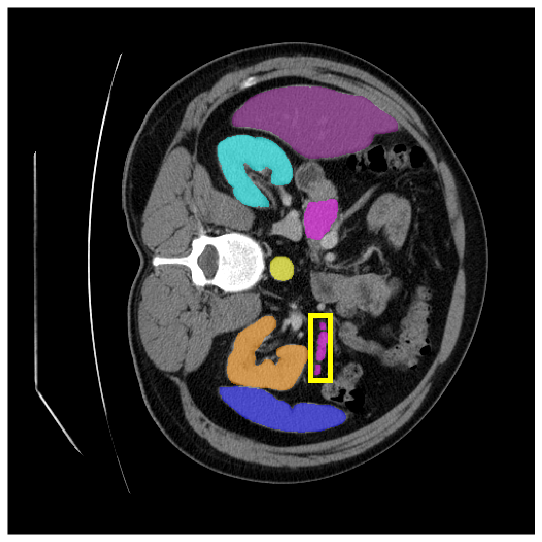

Our model is evaluated on the Synapse [25] and ACDC [24] datasets. Synapse is an abdominal CT image dataset with 30 images containing eight organs: the aorta, gallbladder (GB), left kidney (KL), right kidney (KR), liver, pancreas (PC), spleen (SP), and stomach (SM). 18 and 12 scans are used for training and evaluation, respectively. ACDC provides MRI data containing three organs of 100 patients: the right ventricle (RV), left ventricle (LV), and myocardium (Myo). 70 images for training, 10 for validation, and 20 images for evaluation are used.

4.3.2 Visual Comparisons

Visualization of our method on the Synapse and ACDC datasets is shown in Fig. 3(a) and Fig. 3(b). For the Synapse dataset illustrated in Fig. 3(a), FCT failed to accurately segment SM and GB, while MERIT achieved precise segmentation of SM but struggled with GB. In contrast, our method achieved accurate segmentation of both SM and GB. Regarding the ACDC dataset shown in Fig. 3(b), while previous methods achieve comparable segmentation of the Myo and LV to the GT, they exhibit noticeable errors on the RV, including invasion into adjacent organs and misrecognition. On the other hand, our method accurately segments across all three structures Myo, LV, and RV, performing as precisely as the GT. We demonstrate the superiority of our method quantitatively and qualitatively.